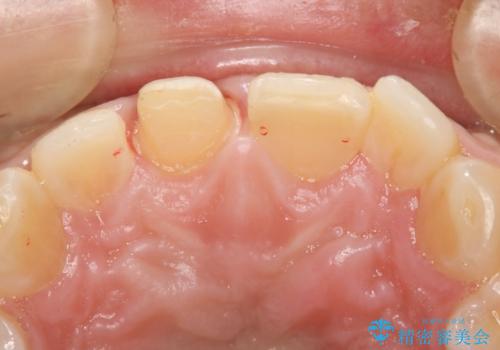

- 上の前歯の一部が欠けてしまったので治療を希望し来院された患者様です。

破折状態から歯髄(歯の神経)は保存できると判断し、クラウンでの治療を計画しました。